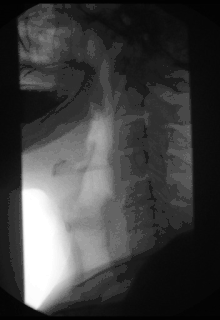

فلوئوروسکوپی یا فلوروسکوپی (به انگلیسی: fluoroscopy) یک روش تصویربرداری است که در علوم تشخیصیِ رادیولوژی و فیزیک پزشکی کاربرد فراوانی دارد.[1]

یک فلوئوروسکوپ متشکل از یک مولد اشعه ایکس با جریان مولد بین ۱ تا ۵ میلی آمپر (و حتی کمتر) است که پرتوهای آن توسط نوعی گیرنده بهنام دستگاه تقویت تصویر[پانویس 1] دریافت و تقویت میشود. این دستگاه پرتوهای ایکس عبوری از درون بدن بیمار را بهصورت زنده[پانویس 2] آشکارسازی میکند و سپس سیگنالهای دریافتشده توسط یک سیستم تلویزیونیِ مداربسته مشاهده و ضبط میشوند.[2]

تکنیکهای فلوئوروسکوپی هنگامی مفیدند که لازم است حرکتی مانند جابجایی مواد در مجرای گوارشی پس از بلعیدن مواد کنتراست زا (مثل باریم) مطالعه شود. در این روش بهجای فیلم از صفحات شیشهایِ فلورسانسِ قابل رؤیت استفاده میشود که باعث مرئی کردن تصویر درهنگام تشعشع رادیوگرافی میشود.

فلوروسکوپی و آنژیوگرافی کاربردهای خاصی از تصویربرداری با اشعه ایکس هستند که در آن صفحه نمایش فلورسنت و یک تیوب یا لوله تشدیدکنندهٔ تصویر، به یک سیستم تلویزیون مدار بسته متصل میشود. سیستمهای جدیدتر از آشکارسازهای فلت پانل استفاده میکنند. این مجموعه امکان تصویر برداری طی یک زمان واقعی از ساختارهای در حال حرکت را فراهم میسازد و در عین حال میتواند با تقویت یک ماده حاجب یا واسطه نیز همراه گردد. تصاویر اشعه ایکس میتوانند برای بررسی بر روی یک فیلم هم ثبت گردند. اما موقعی که مشاهده حرکت یک شی مثلاً مشاهده حرکت ماده حاجب در مسیر گوارشی مورد نظر است میتوان مستقیماً تصویر را بر روی یک صفحه مونیتور بهطور زنده مشاهده نمود.[3]